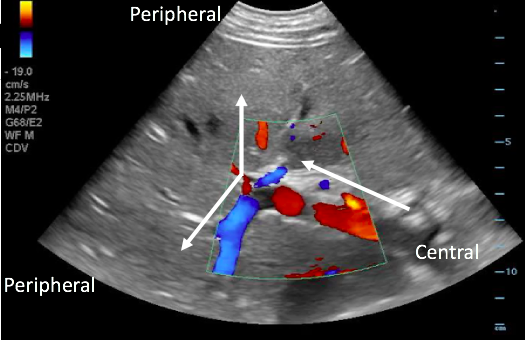

- Physiologic blood flow in the portal vein is from deep (the spleen and intestines) to superficial (the liver periphery), towards the probe.

- With the probe on the anterior abdominal wall, blood in the portal vein flows from central (the mesenteric and splenic veins) towards the liver and will be red when color Doppler is applied. The middle and left portal venous branches will still appear red. However, blood in the right portal venous branch will flow deep into the right lobe, appearing blue.

Figure 17. Color Doppler image with arrows illustrating normal portal venous blood flow, from the center towards the periphery of the liver.

- May indicate portal hypertension, as increased pressure forces blood back towards the spleen and intestines

- Blue flow (away from probe) in the portal vein on color Doppler.

- Color Doppler may serve as a useful screening tool.